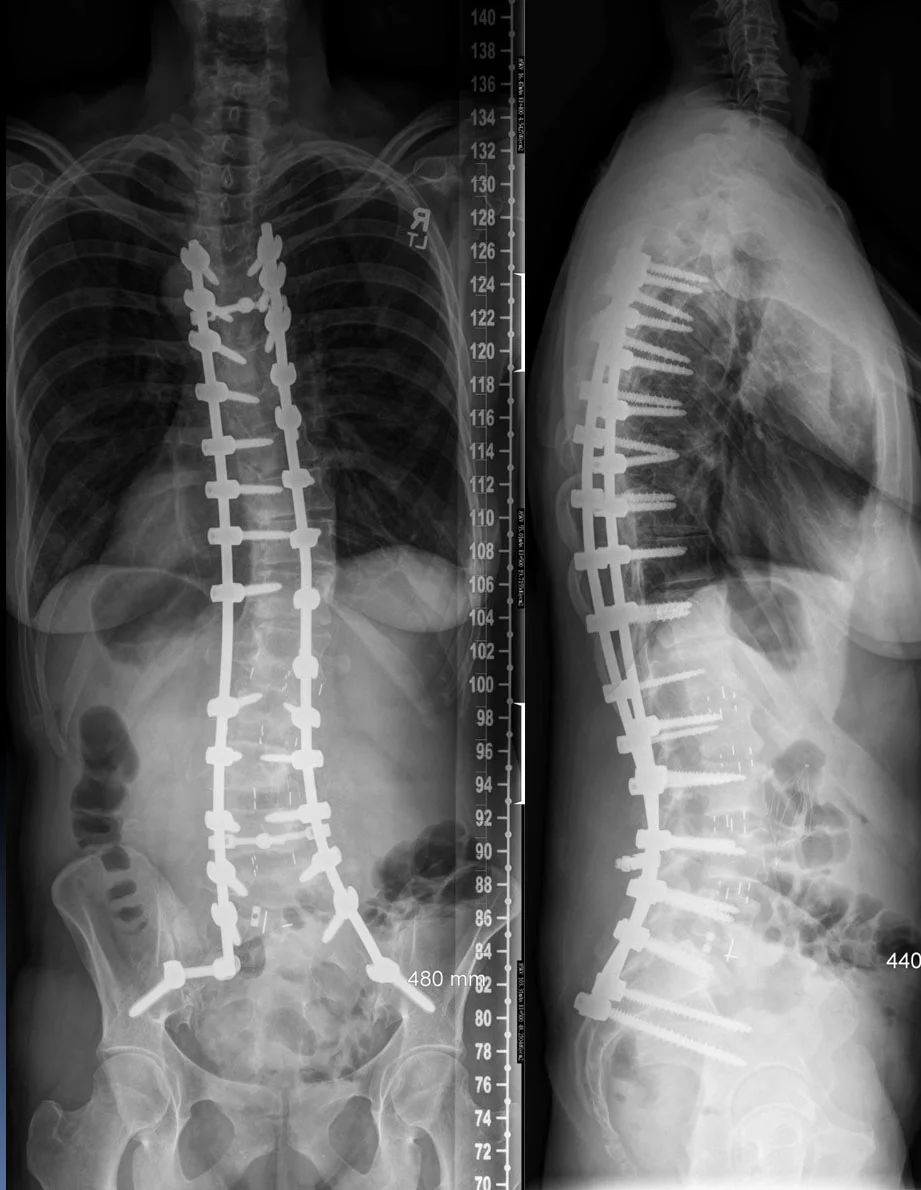

The case below shows a 46-year-old female with untreated adolescent scoliosis. As a result, she experienced a loss of height from 5'11" to 5'5". She is decompensated forward and to the right. She is experiencing disabling back pain. She was treated in two stages with lateral lumbar inter-body fusions followed by posterior spinal fusion, pedicle screw and rod fixation, and ponte osteotomies. She gained 3 inches in height, has relief of her back pain, and has significant improvement in her posture.